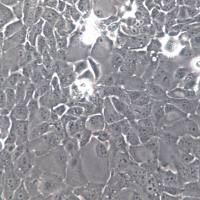

NCI-H1373

肺

人

- 细胞形态:

上皮细胞样

T25培养瓶/冻存管